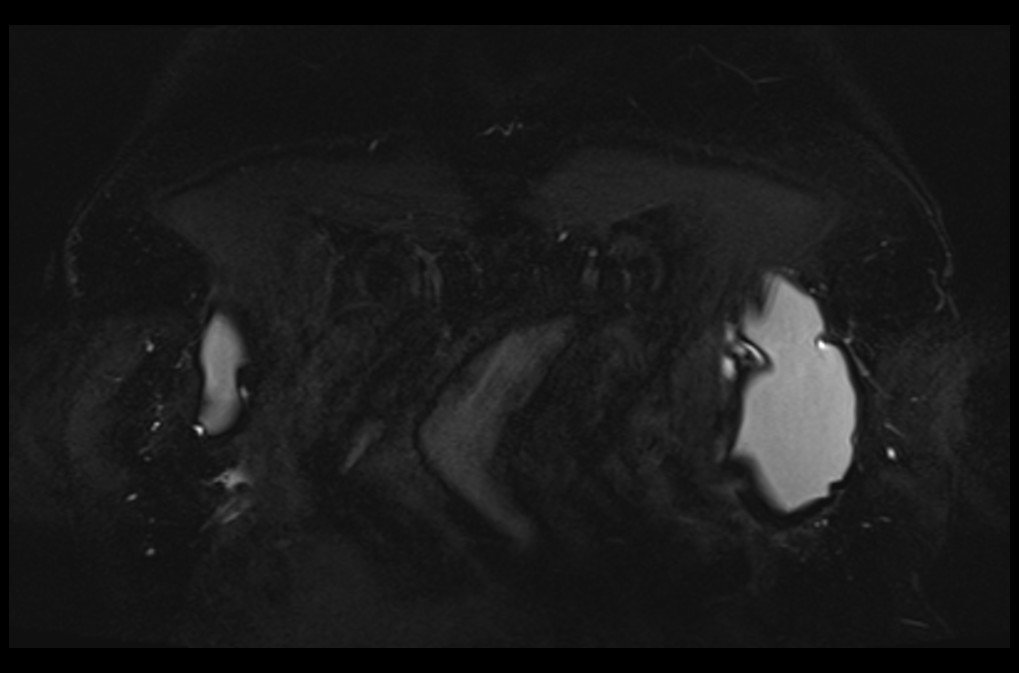

MRI breast implant stir coronal images 1 - MRI